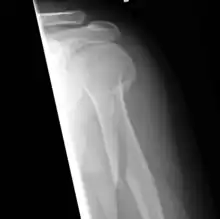

An x-ray image of a spiral fracture to the left humerus

An x-ray image of a spiral fracture to the left humerus of a 27-year-old male. The injury was sustained during a fall.